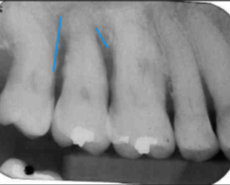

moderate to severe horizontal bone loss

horizontal bone loss

parallel movement of alveolar crests towards the apex of the tooth

loss of height around multiple teeth may involve furcation

moderate horizontal bone loss